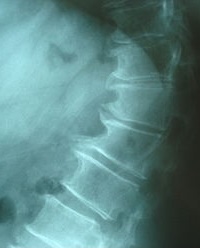

Thoracic Spondylosis.JPG

داء الفقارا لصدري